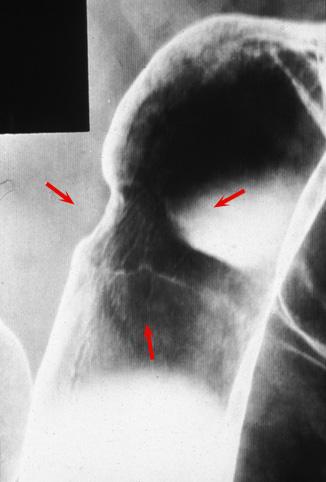

疾病(病理主体)的分类恶性上皮性肿瘤/腺癌

部位(按器官分)大肠/横结肠

检查方法X线

肿瘤的肉眼分类3型(溃疡浸润型)/

肿瘤最大直径25~29

肿瘤的深度mp